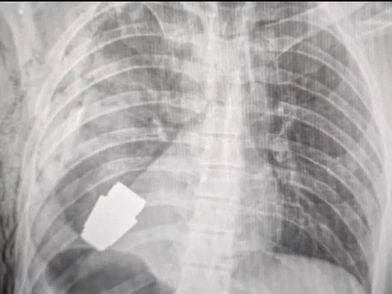

Την είδηση, που αναδημοσιεύει το βρετανικό δίκτυο BBC, γνωστοποιήθηκε από ανάρτηση που έκανε η σελίδα της ιατρικής υπηρεσίας των Ενόπλων Δυνάμεων της Ουκρανίας στο Facebook, όπου φαίνεται η ακτινογραφία με καρφωμένη τη χειροβομβίδα στο στήθος του στρατιώτη. Στην ανάρτηση, μάλιστα, φαίνεται και ο χειρουργός που ανέλαβε την εγχείρηση να κρατά τη χειροβομβίδα, λίγα λεπτά αφότου την αφαίρεσε. Την εγχείρηση φέρεται πως επέβλεπαν δύο στρατιώτες, προκειμένου να βεβαιωθούν ότι έγινε με ασφάλεια.

Στη σχετική ανάρτηση υπογραμμίζεται ότι η επέμβαση πραγματοποιήθηκε χωρίς τη χρήση ηλεκτροπήξης -μια κοινή μέθοδο όπου χρησιμοποιείται ηλεκτρικό ρεύμα για να βοηθήσει στον έλεγχο της αιμορραγίας κατά τη διάρκεια της επέμβασης- επειδή τα πυρομαχικά θα μπορούσαν να εκραγούν ανά πάσα στιγμή. Πρόσθεσε ότι η συσκευή ήταν μια χειροβομβίδα VOG - ένα κομμάτι πυρομαχικών μήκους 4 εκατοστών που εκτοξεύεται από έναν εκτοξευτήρα χειροβομβίδων και μπορεί να φτάσει περίπου 400 μέτρα μακριά και είναι σχεδιασμένο να εκρήγνυται ακριβώς πάνω από το έδαφος.